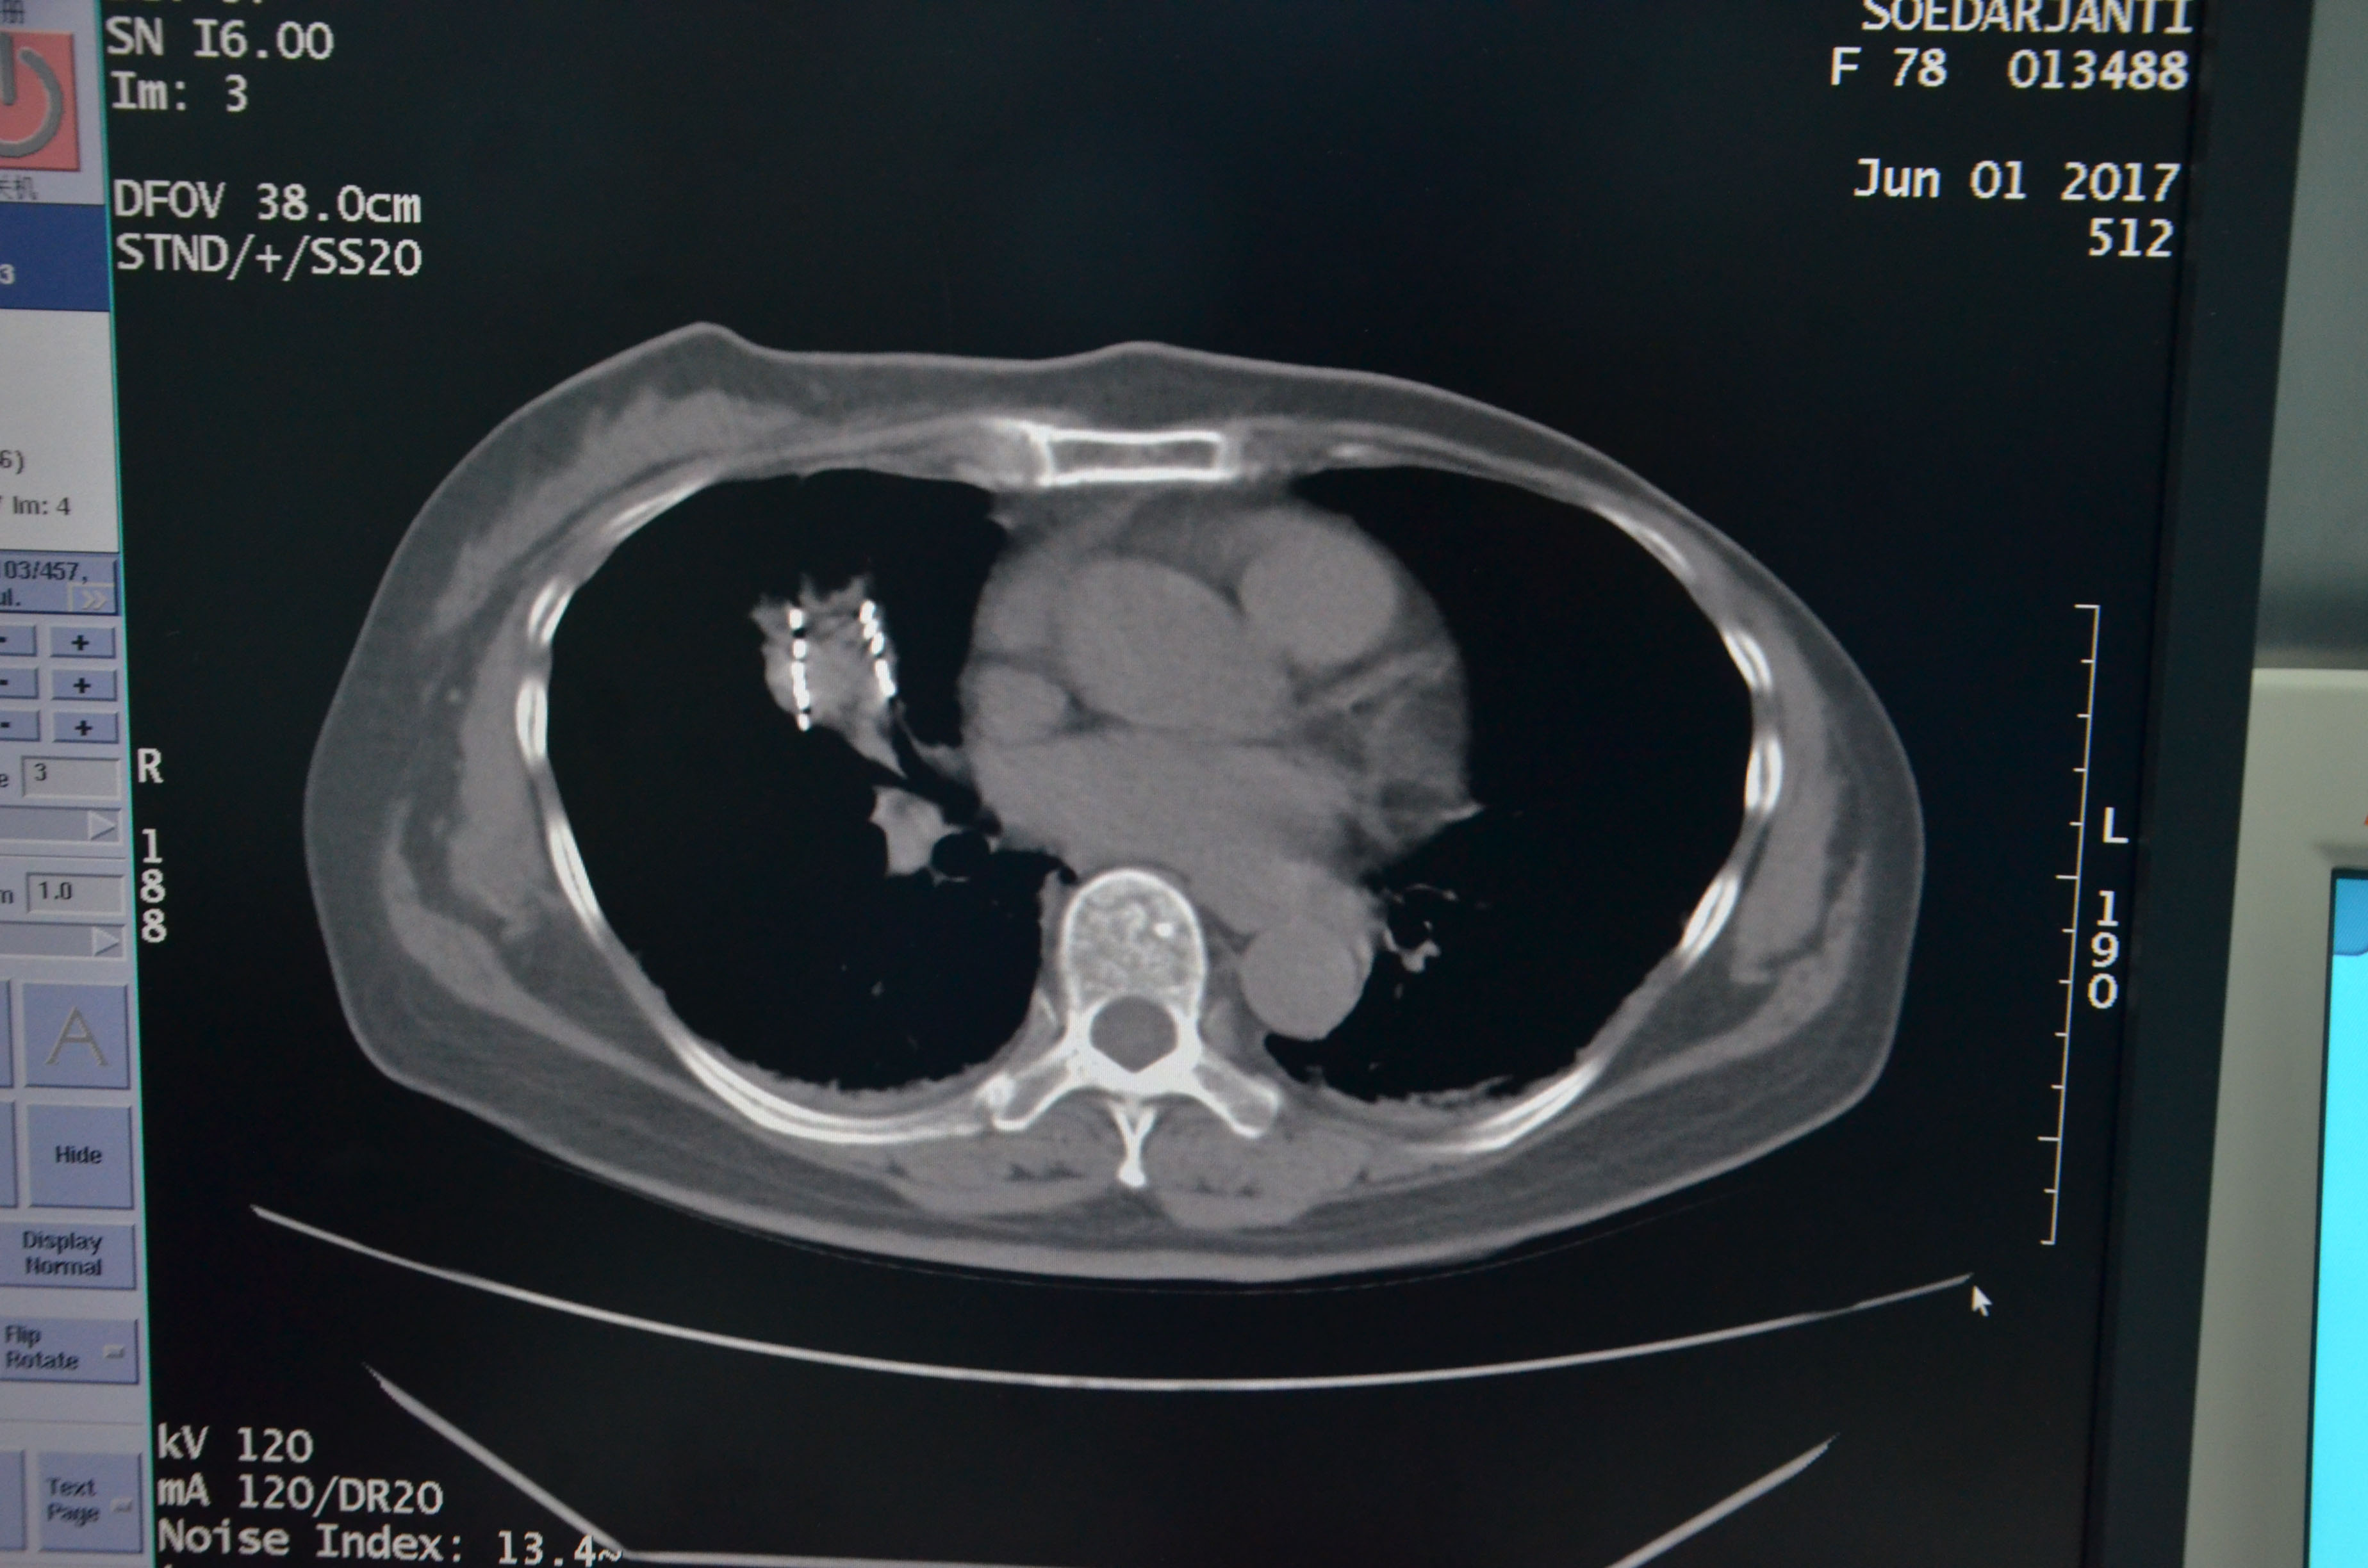

6月1日,医院成功为该患者实施3D微创导向模板引导下的I 125粒子植入,术后患者身体状况良好,病情控制稳定。对粒子的分布作出剂量分析,完全符合术前的组织计划剂量。

▲术后粒子分布,与术前组织计划剂量吻合